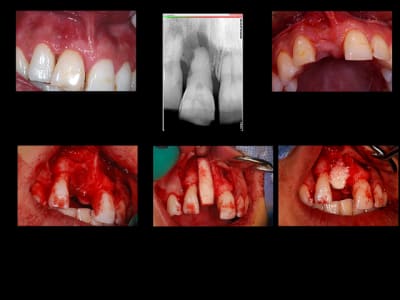

encore un ptit cas...sympa si on veut...car là j'ai besoin de l'expérience de ceux qui font çà souvent...

patient 17 ans...bientôt 18...

trauma dans l'enfance sur 11 et 21

pour la 21, çà va...mais la 11 est à bout de souffle...avec l'apex qui traverse la gencive vestibulaire...

veut un implant...forcément...mais là, faut une greffe...plutôt importante...

je pencherais plutôt pour un bloc fixé avec des vis d'ostéosynthèses...par contre, je suis pas chaud (et lui non plus) pour aller prélever au menton ou sur la branche montante...